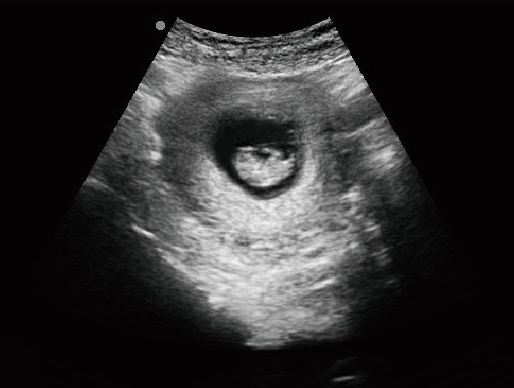

MU15便携式兽用B超机

全数字兽用超声诊断仪

·具有专业的动物产科软件包,分别是狗、猫、马、牛、羊

牛羊马猪犬猫及多种家禽、实验动物、野生动物、及部分水生动物

·适用于各种动物的临床腹部、胸腔,心脏、肌腱、小器官、眼球、生殖系统等的检查